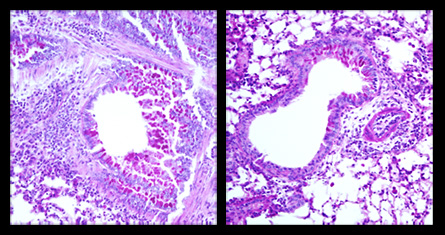

In normal mice, the injection causes T cells to attack lung tissue, leading to extreme airway inflammation. By contrast, mice lacking the DR3 receptor had much less lung inflammation.

To mimic multiple sclerosis in the mice, the group used a similar method, this time inoculating nerve cells rather than the lungs. In normal mice, this method drove T cells to destroy the sheaths covering nerve cells, paralyzing the mice. The knockout mice, by contrast, did not have such nerve damage.